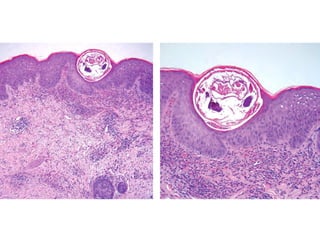

The document references a verse from the Quran (Al-A'raf: 133) discussing the plagues sent as signs to a people who were arrogant and sinful. It mentions various afflictions such as locusts, blood, frogs, and lice. The context highlights the consequences faced by those who rejected the divine signs.